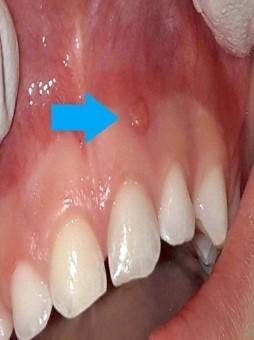

Στην συγκεκριμένη περίπτωση η παρουσία οδοντωμάτων εμποδίζει την ανατολή των μόνιμων κεντρικών τομέων καθιστώντας τα έγκλειστα.

H έγκαιρη παρέμβαση λύνει το πρόβλημα με την χειρουργική απομάκρυνση των οδοντομάτων και με την υποβοηθούμενη μετατόπιση των κυρίως δοντιών με ορθοδοντικές δυνάμεις.